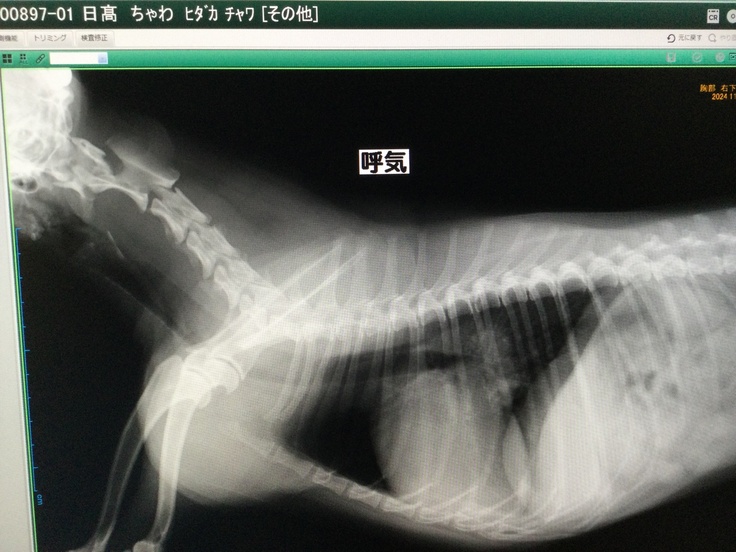

11/25のレントゲン画像

11月25日の検査の結果、前回の検査時よりも体重が300g減り、咳が増え、また肺に影がうっすら出てきており、肺水腫になりかけているとのことでした。

こちら↑は11月25日に普段のかかりつけ動物病院での通院検査費です。(手術を受ける病院とは別になります。)